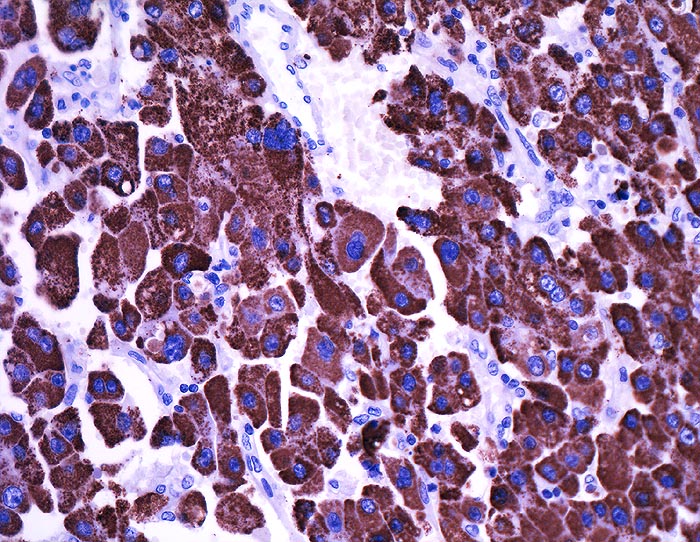

Hepatozelluläres Karzinom : Ovarmetastase

Die hepatozytenähnlichen Anteile der Metastase reagieren sehr stark mit dem hepatozellulären Marker Hep-Par1

St.n. Lebertransplantation wegen Hepatozellulärem Karzinom bei Hepatitis C vor 2 Jahren. Jetzt Metastasen von 12 und 14cm Durchmesser in beiden Ovarien.

Histologie

Immunhistochemie

Hep-Par 1, Hepatocyte